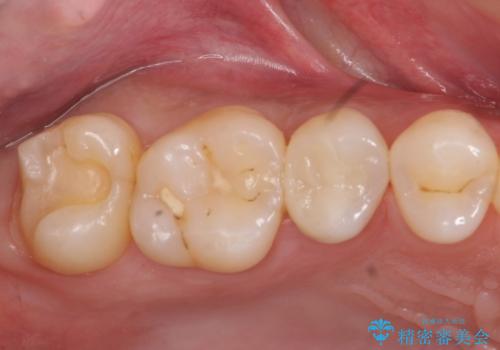

奥歯の虫歯 セラミックインレーに

- 上の奥の虫歯をセラミックインレーで修復しました。

特に自費のインレーの適合(歯にぴったり合っている)はとても良く、虫歯になりにくいです。

高価なようで、実は将来のことを考えた歯を残す治療の第一歩です。